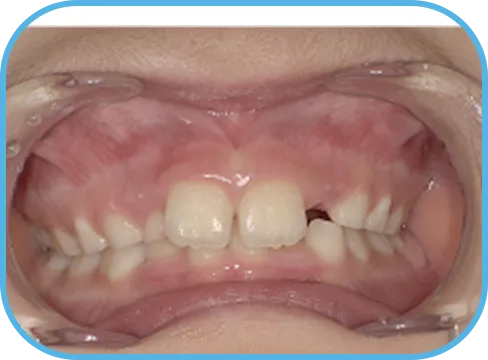

• Before

• 正 面

治療前正面からの歯の様子

• After

治療後正面からの歯の様子

主 訴

前歯ガタガタ、前歯が大きい

治療内容

インビザライン・ファースト

治療期間

7か月

治療費(税別)

450,000円+診断料5,000円

リスク・副作用

• 親知らずの影響や加齢などによって、凸凹が生じる可能性があります。

• 治療の初期段階では痛みや不快感が生じやすくなりますが、1週間前後で慣れます。

• 顎の成長発育によって、噛み合わせや歯並びが変化する可能性があります。

• 状況により当初予定した治療計画を変更する可能性があります。